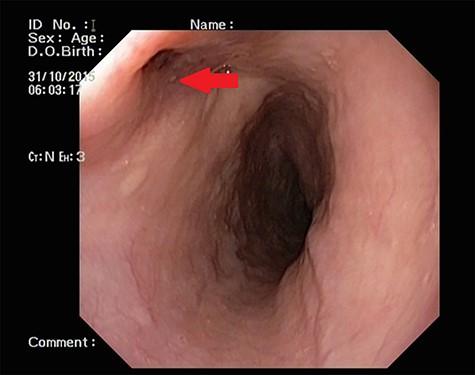

Patient 1: a 52-year-old woman, non-diabetic, non-hypertensive, was referred to the emergency with a history of large-volume, frank hematemesis (four episodes in 3 days). Positive history included recurrent cough for the past 1 year and low-grade fever for 3 months. No history of dysphagia, jaundice, abdominal distension, pain abdomen or altered sensorium. No history of chronic medications (oral anticoagulants or anti-platelets), analgesic intake or any substance abuse. She had received four units of packed red cells at an outside facility prior to admission. She was conscious, oriented, hemodynamically labile (heart rate: 110/min; BP: 86/60 mm Hg) with mild fever (99°F). General survey revealed obvious pallor. All other system examinations were within acceptable limits. Her hemoglobin (Hb) was 7.3 gram%, total leukocyte count (TLC) was 6400 cells/mm3, total bilirubin was 1.31 mg/dl and total protein was 4.75 gram%. An urgent UGI endoscopy revealed an opening in the posterior wall of the lower third of the esophagus, with a diverticulum. Inflammatory changes were noted in the diverticulum (Fig. 1). Contrast-enhanced computed tomogram (CECT) revealed erosion of the pouch into the thoracic aorta (Fig. 2), and a diagnosis of AEF with acute UGI hemorrhage was made.

UGI endoscopy showing a large depressed ulcer located in the middle third of the esophagus; a diverticulum was seen in the lower end of the ulcer (red arrow).

Patient 2: a 48-year-old hypertensive, non-diabetic gentleman, presented to the emergency with one episode of massive hematemesis. There was no history of dysphagia, jaundice, abdominal distension, pain abdomen or altered sensorium. Past history was significant for percutaneous coronary intervention with two drug-eluting stents performed 3 years ago, for which he was on aspirin. He had normal mentation, his BP was 90/60 mm Hg and his heart rate was 120/min. A general survey revealed pallor and rest of the systemic examination was normal. His Hb was 6.1 gram% and TLC was 6300 cells/mm3. Liver function tests, coagulation parameters, renal function and electrolytes were normal. Chest X-ray was unremarkable. He was initially resuscitated with intravenous fluid, packed red blood cells and a proton-pump inhibitor infusion. An urgent UGI endoscopy revealed a large depressed ulcer with a red spot located in the middle third of the esophagus. A diverticulum was seen in the lower end of the ulcer (Fig. 7). An endoscopic clip was applied to the margin for ease of identification. CECT thorax revealed a 6 cm saccular thoracic aortic aneurysm distal to the left subclavian artery, eroding into the esophagus (Fig. 8).